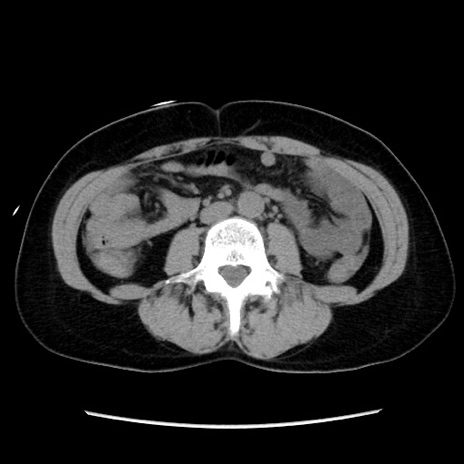

症例10(横断像)

【症例】 50歳代女性

【主訴】 腹痛

【現病歴】前日生レバーを食べた。今朝に排便あり。 昼前に突然発症の腹痛を生じ、当院救急外来を受診した。

【既往歴】 子宮筋腫にてで子宮全摘後

【身体所見】 意識清明、腹部:平坦、軟、下腹部やや左を中心に圧痛・反跳痛あり、筋性防御あり

【データ】WBC 7800、CRP 0.07